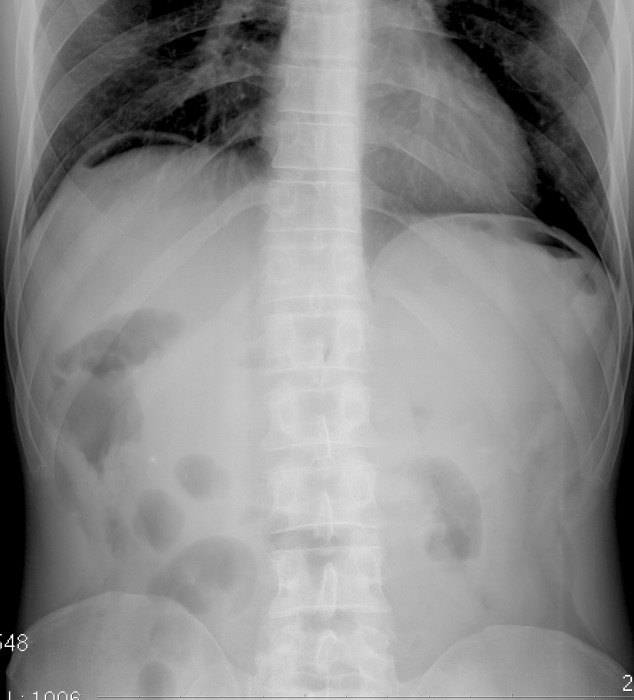

Необычные находки: инородные тела на рентгенограмме брюшной полости